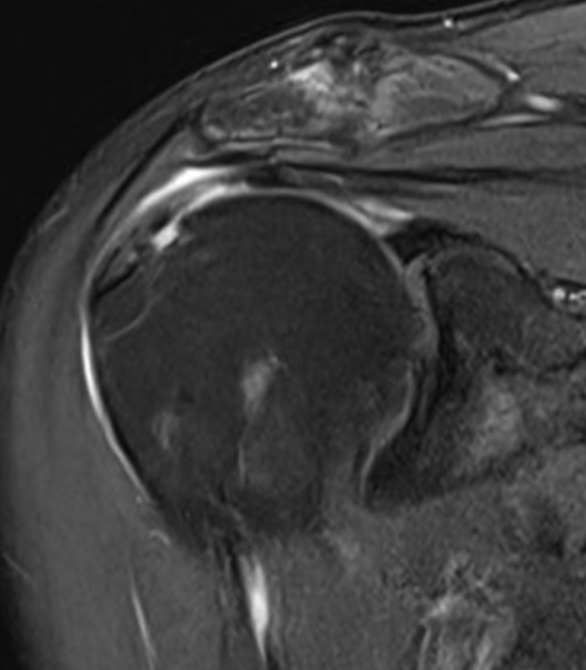

Full thickness rotator cuff tears

Measure tear in the coronal and sagittal plane

Small full thickness rotator cuff tear of supraspinatus - retracted to footprint

Large full thickness tear of supraspinatus and infraspinatus tendon - retracted to midhumeral head

Massive rotator cuff tear of the supraspinatus and infraspinatus tendon - retracted to glenoid